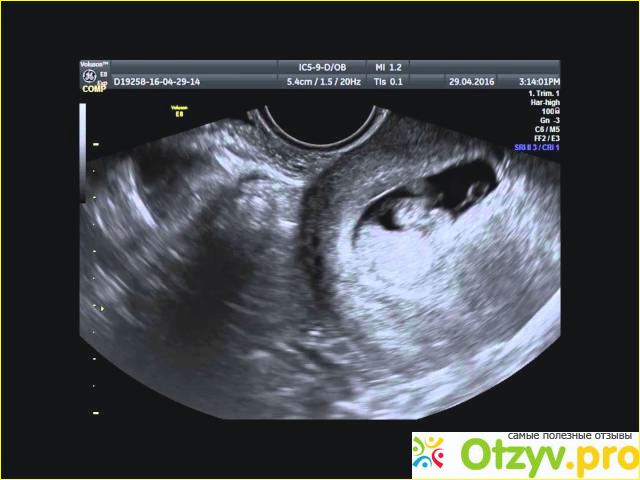

• Замершая беременность: причины, признаки -  - Фото 366234